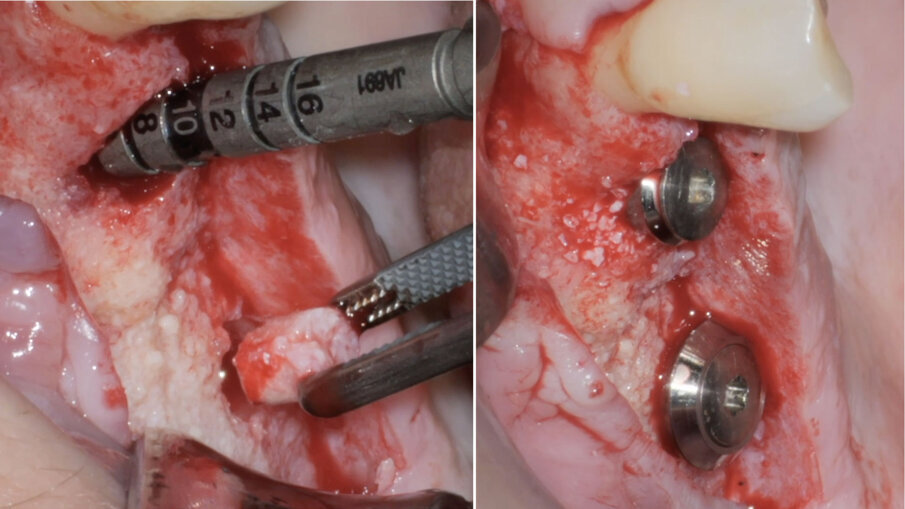

Pertanto, in anestesia locale, si esegue un’incisione a busta in sede 1.8-1.4 con scarico mesiale, si scheletrizza il mascellare superiore isolando per via smussa la deiscenza del pavimento sinusale in sede 1.5 (Fig. 3), e si procede all’estrazione del dente 1.4 e dell’impianto 1.7 ed alla degranulazione dei difetti post-estrattivi. Segue pertanto una opercolizzazione ossea in sede 1.6, con scollamento della membrana di Schneider e creazione di uno spazio subsinusale esteso fino alla deiscenza in 1.5 (Fig. 4). Segue quindi un primo apporto di Regenfast sul letto osseo ricevente e il riempimento dello spazio subsinusale con Geistlich Bio-Oss (Geist-lich Pharma) granulometria small. Segue la stabilizzazione vestibolare di una membrana Geistlich Bio-Gide (Geistlich Pharma) con pins in titanio, e il posizionamento di Geistlich Bio-Oss a ricostruzione del difetto in sede 1.5 ed 1.4. La membrana viene quindi ribattuta sull’aspetto palatale della cresta, e stabilizzata con una combinazione di pin in titanio e suture a materassaio palatali.

Fig. 3 - Scheletrizzazione del lembo, visione vestibolare.

Fig. 4 - Opercolizzazione ossea e scollamento della membrana di Schneider.